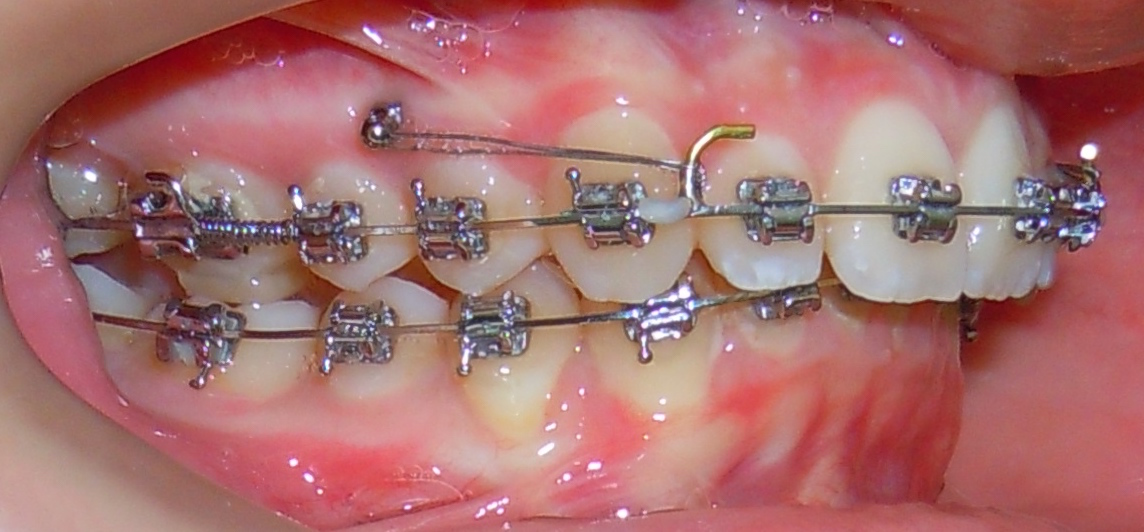

Connection to brackets or aligners via elastics or springs. The mini-screw works silently 24/7.

Connected to brackets or aligners via elastics or springs, it exerts a constant and controlled force.

Compatible

Works equally well with traditional brackets and clear aligners.